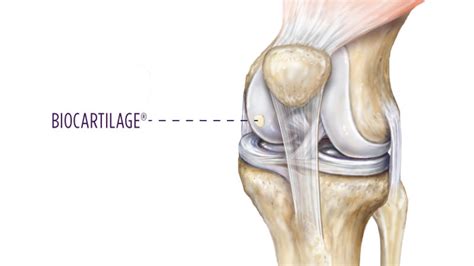

Detailed view of human knee anatomy

The cartilage found in the knee is primarily articular cartilage, a type of hyaline cartilage that covers the ends of the bones. Unlike other tissues in the body, it has a unique composition that allows it to withstand significant compressive forces. It consists of a dense network of collagen fibers and proteoglycans, which attract water to create a gel-like consistency.

Because knee joint cartilage is avascular—meaning it lacks a direct blood supply—it relies on synovial fluid to obtain nutrients and remove waste products. This process, known as imbibition, occurs during the compression and release cycles of movement, which is why consistent, low-impact exercise is essential for its health.